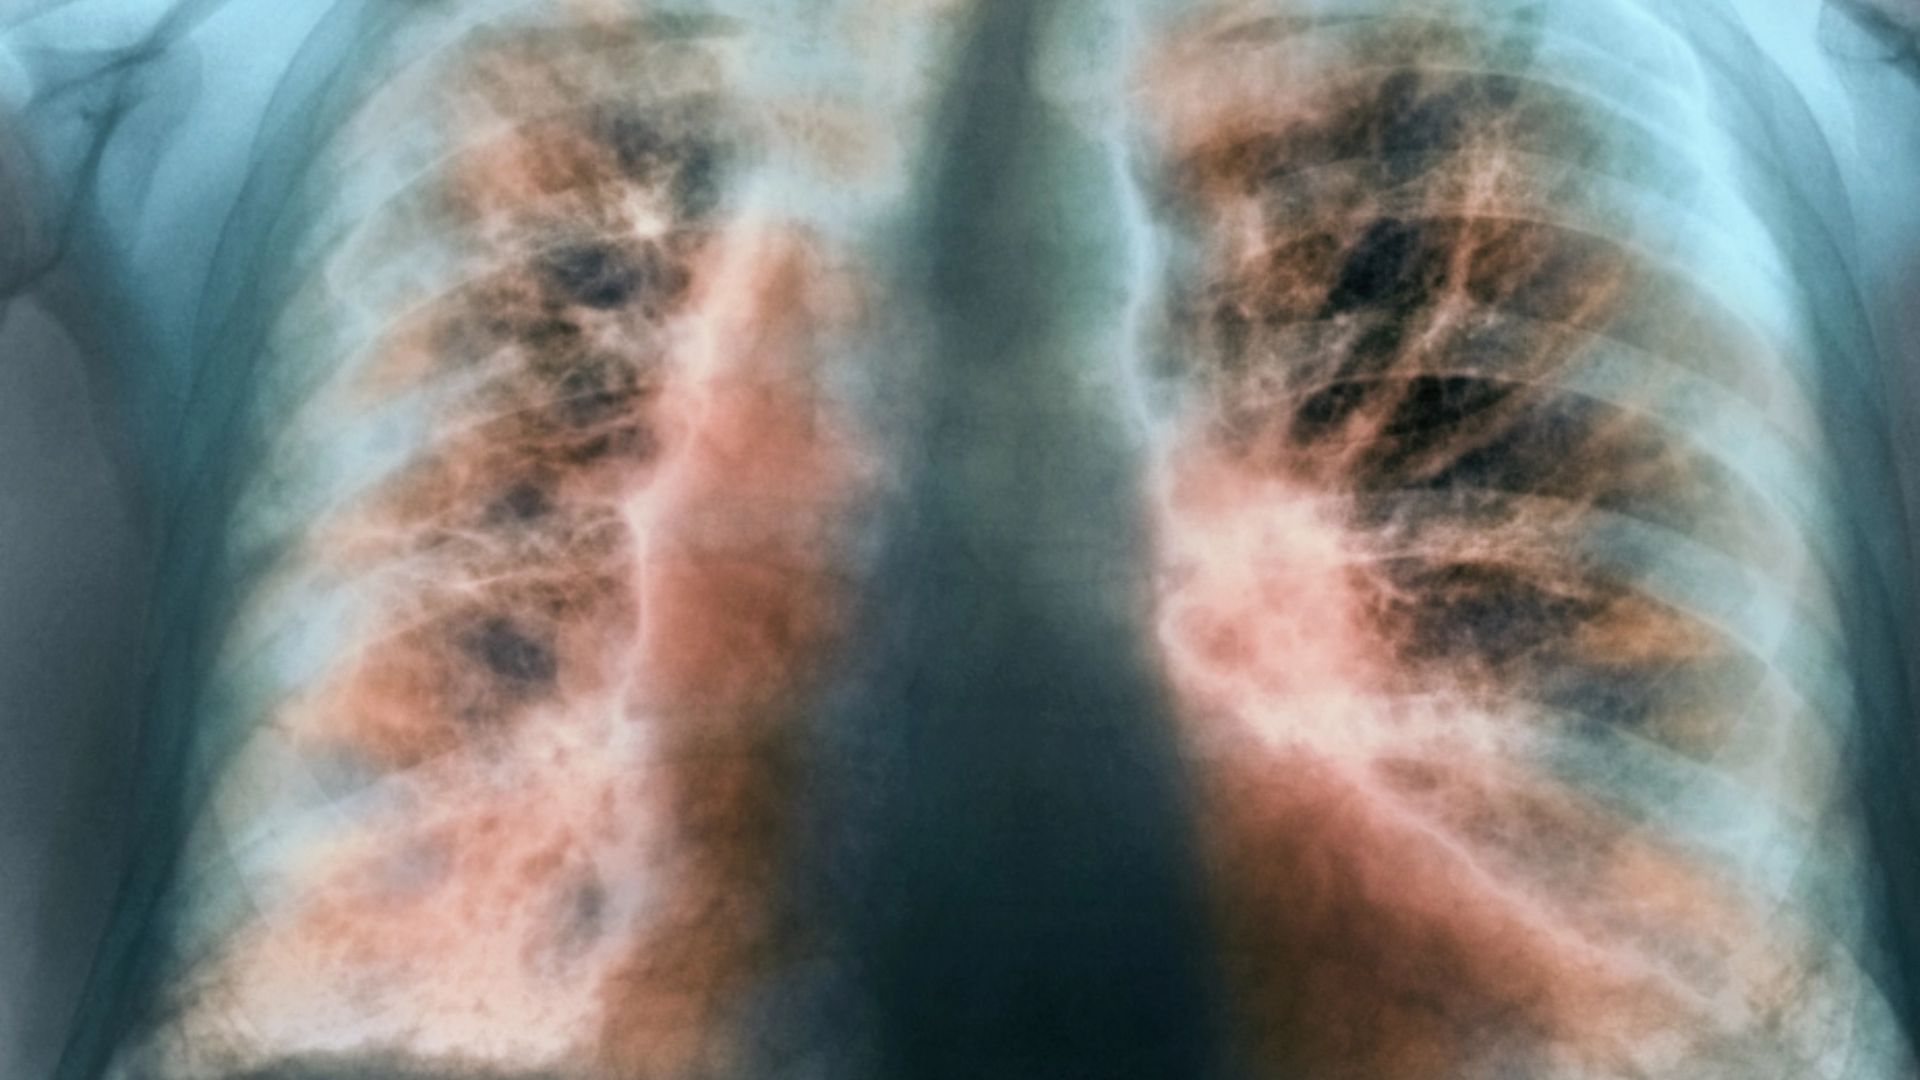

ডা. আব্দুস শাকুর খান বলেন, ফুসফুসের ক্যানসার হচ্ছে ফুসফুসের এক ধরনের টিউমার। অর্থাৎ ফুসফুসের যে স্বাভাবিক কোষ আছে সেই স্বাভাবিক কোষের যখন অস্বাভাবিক এবং অনিয়ন্ত্রিত বৃদ্ধি হয়ে চাকার মত সৃষ্টি করে, তাকেই ফুসফুস ক্যানসার বলে। এটি শরীরের জন্য মারাত্মক ক্ষতিকর। ক্যানসার যখন ফুসফুসে হয় এটা শুধু নির্দিষ্ট জায়গায় থাকে না বরং অস্বাভাবিক এবং অনিয়ন্ত্রিত বৃদ্ধির কারণে শরীরের অন্যান্য অংশেও ছড়িয়ে পড়ে। সঠিক সময়ে শনাক্ত ও যথাযথ চিকিৎসার অভাবে শেষ পর্যন্ত মৃত্যুরও কারণ হয়ে থাকে।

কোষগত এবং চরিত্রগত বিষয় বিবেচনা করে ফুসফুসের ক্যানসারের ধরন নির্ণয় করা হয়। ফুসফুস ক্যানসারকে প্রধানত ২টি ভাগে ভাগ করা হয়। যেমন- স্মল সেল বা ছোট কোষের ফুসফুস ক্যানসার, যেখানে এক ধরনের বিশেষ কোষ থাকে, এই ছোট কোষের ফুসফুসের ক্যানসার বেশি ক্ষতিকারক। আরেকটি ধরন হচ্ছে নন স্মল সেল বা অক্ষুদ্র কোষের ফুসফুসের ক্যানসার।